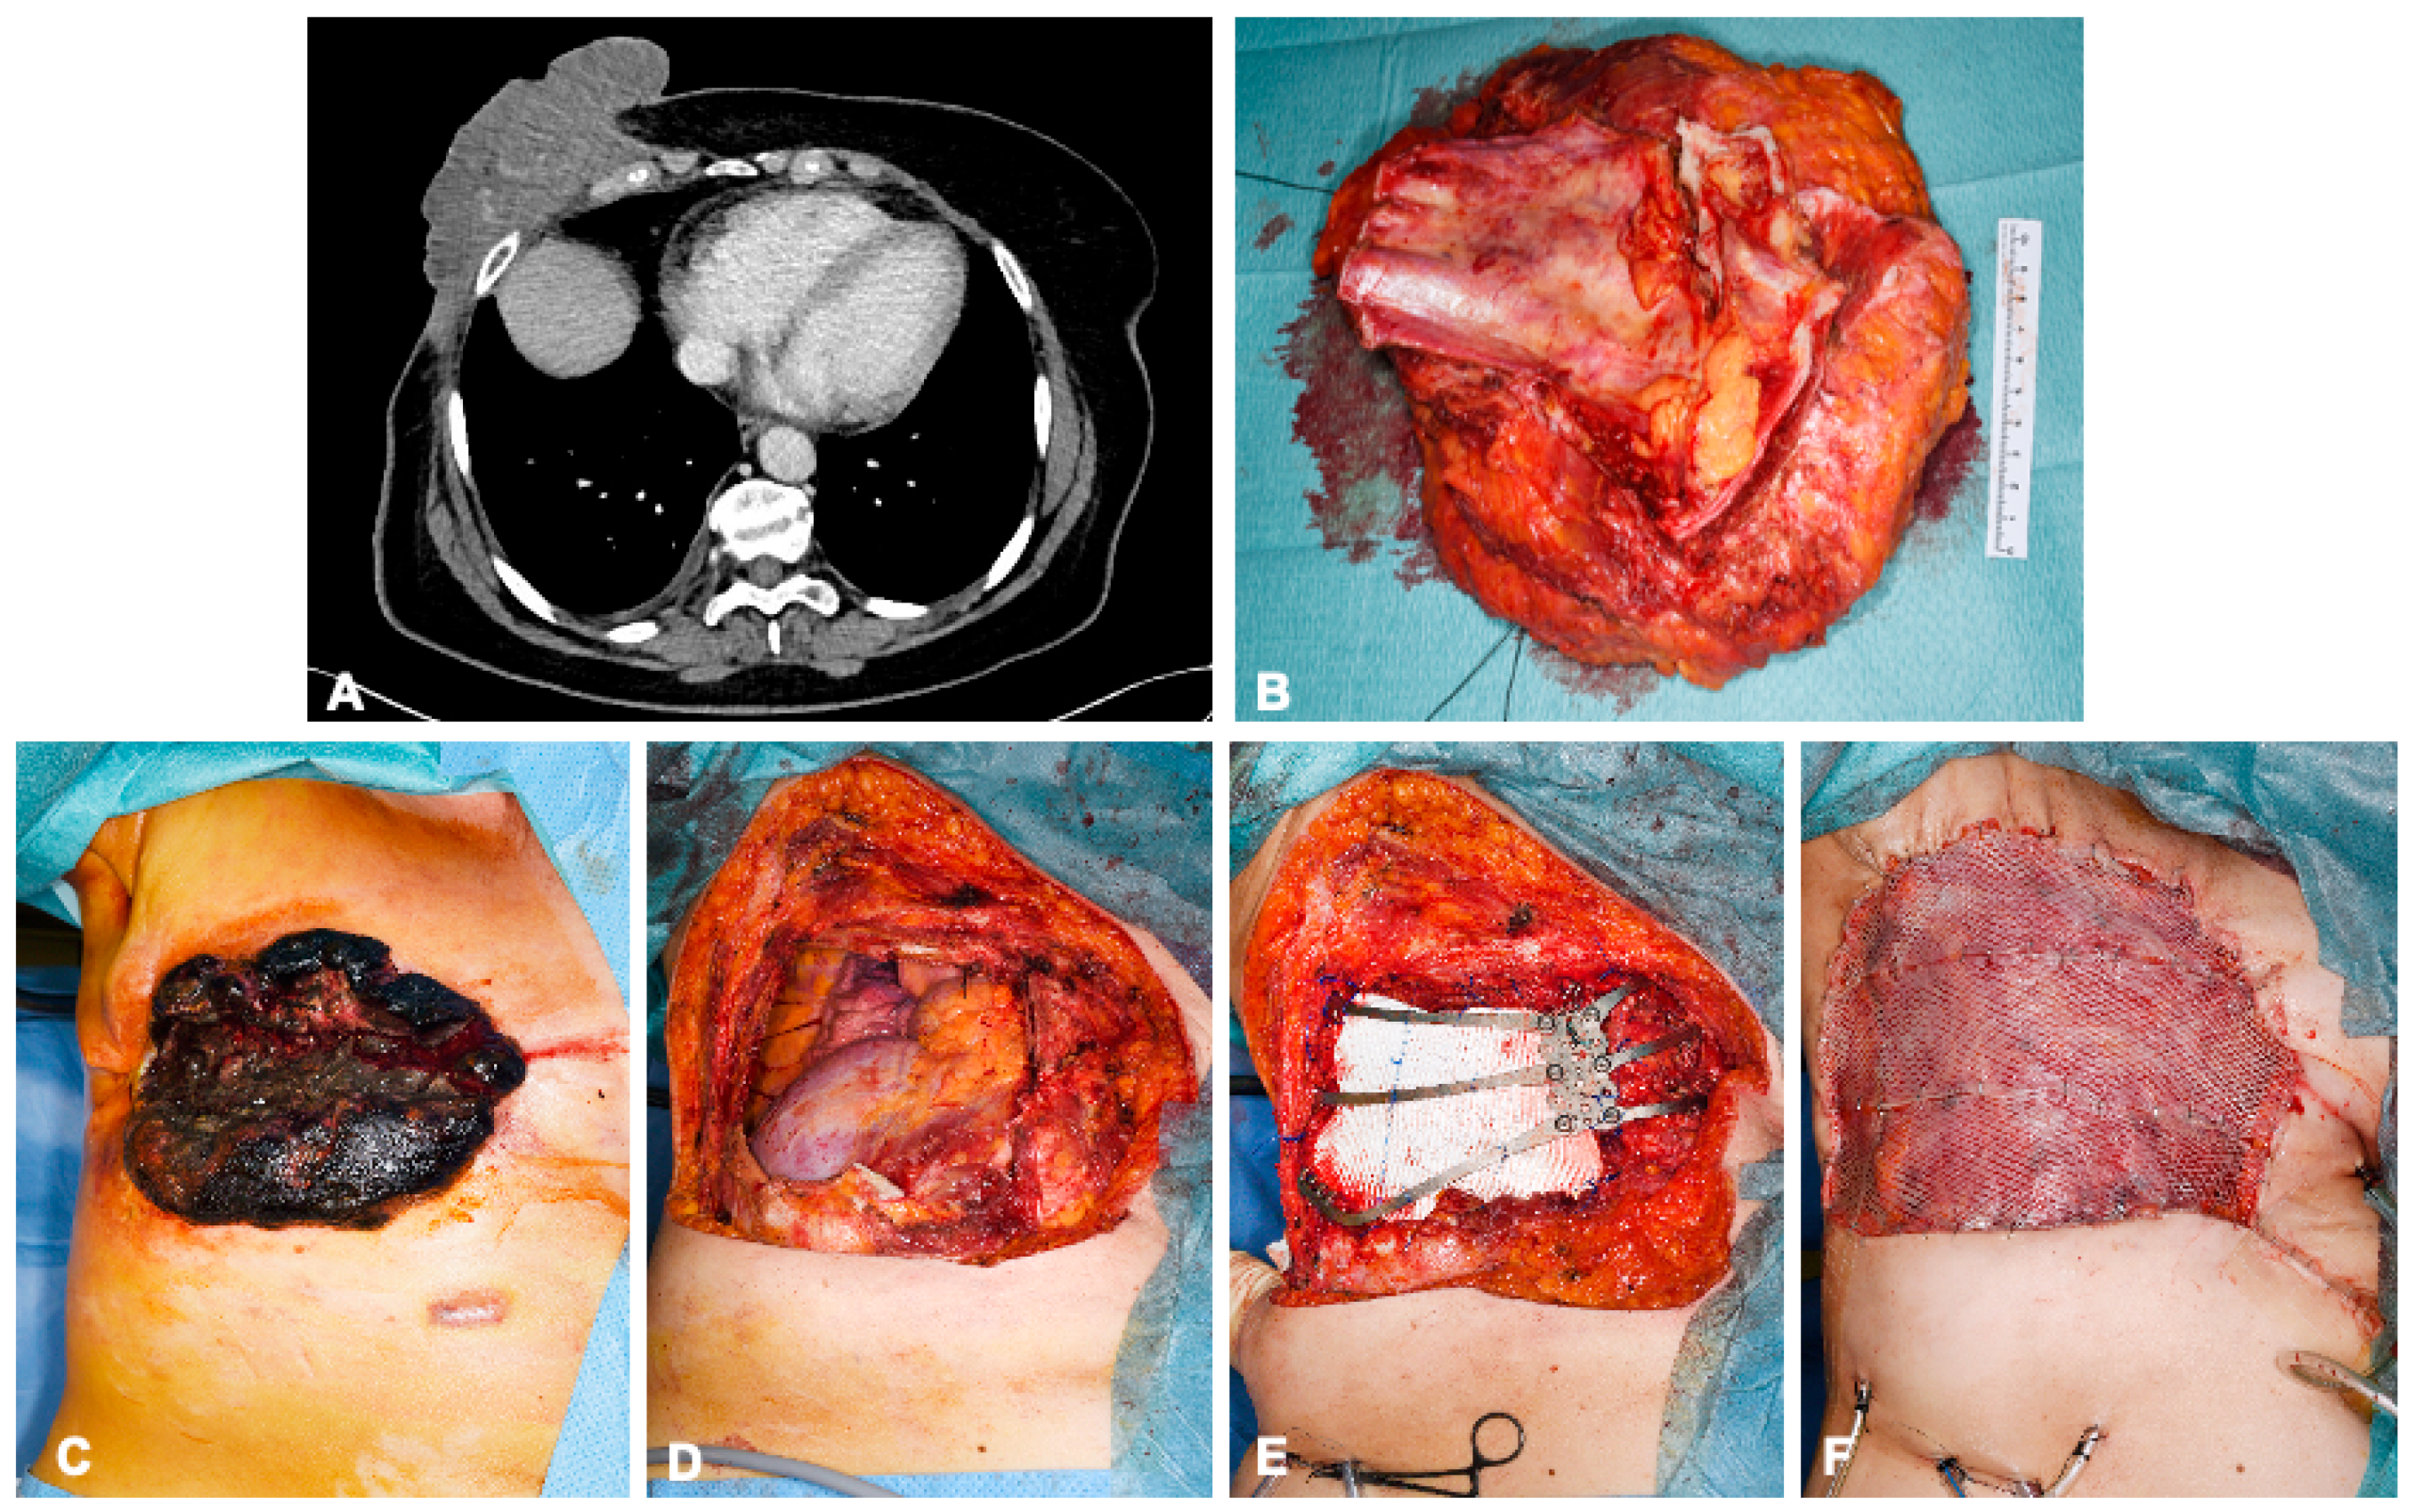

Figure 3.

A 68-year-old female patient with angiosarcoma of the right breast 8 years after receiving radiation therapy for breast carcinoma. Preoperative computed tomography images show involvement of the right thoracic wall with infiltration of the pectoralis major muscle, serratus anterior muscle, and intercostal muscles without distant metastasis (A). En bloc resection of the exophytic tumor-involved soft tissue, the corpus sterni, and parts of ribs 5–7 (B). Reconstruction of the pleura was performed using a Gore-Tex patch and the chest wall with a customizable titanium cage (TRIONYX®, NEURO FRANCE Implants, Clamart, France). The soft tissue defects were covered with a pedicled Latissimus dorsi muscle flap and split skin graft from the right thigh (C–F).